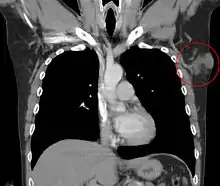

Metastases to regional lymph nodes are extremely rare.[33] Distant hematogenous metastases are even rarer and are most likely in patients who have had multiple local recurrences after inadequate surgical resection.[34] Repeatedly recurring tumors have an increased risk for transformation into a more malignant form (DFSP-FS). The lungs are most frequently affected, but metastases to the brain,[35] bone,[36] and other soft tissues are reported.